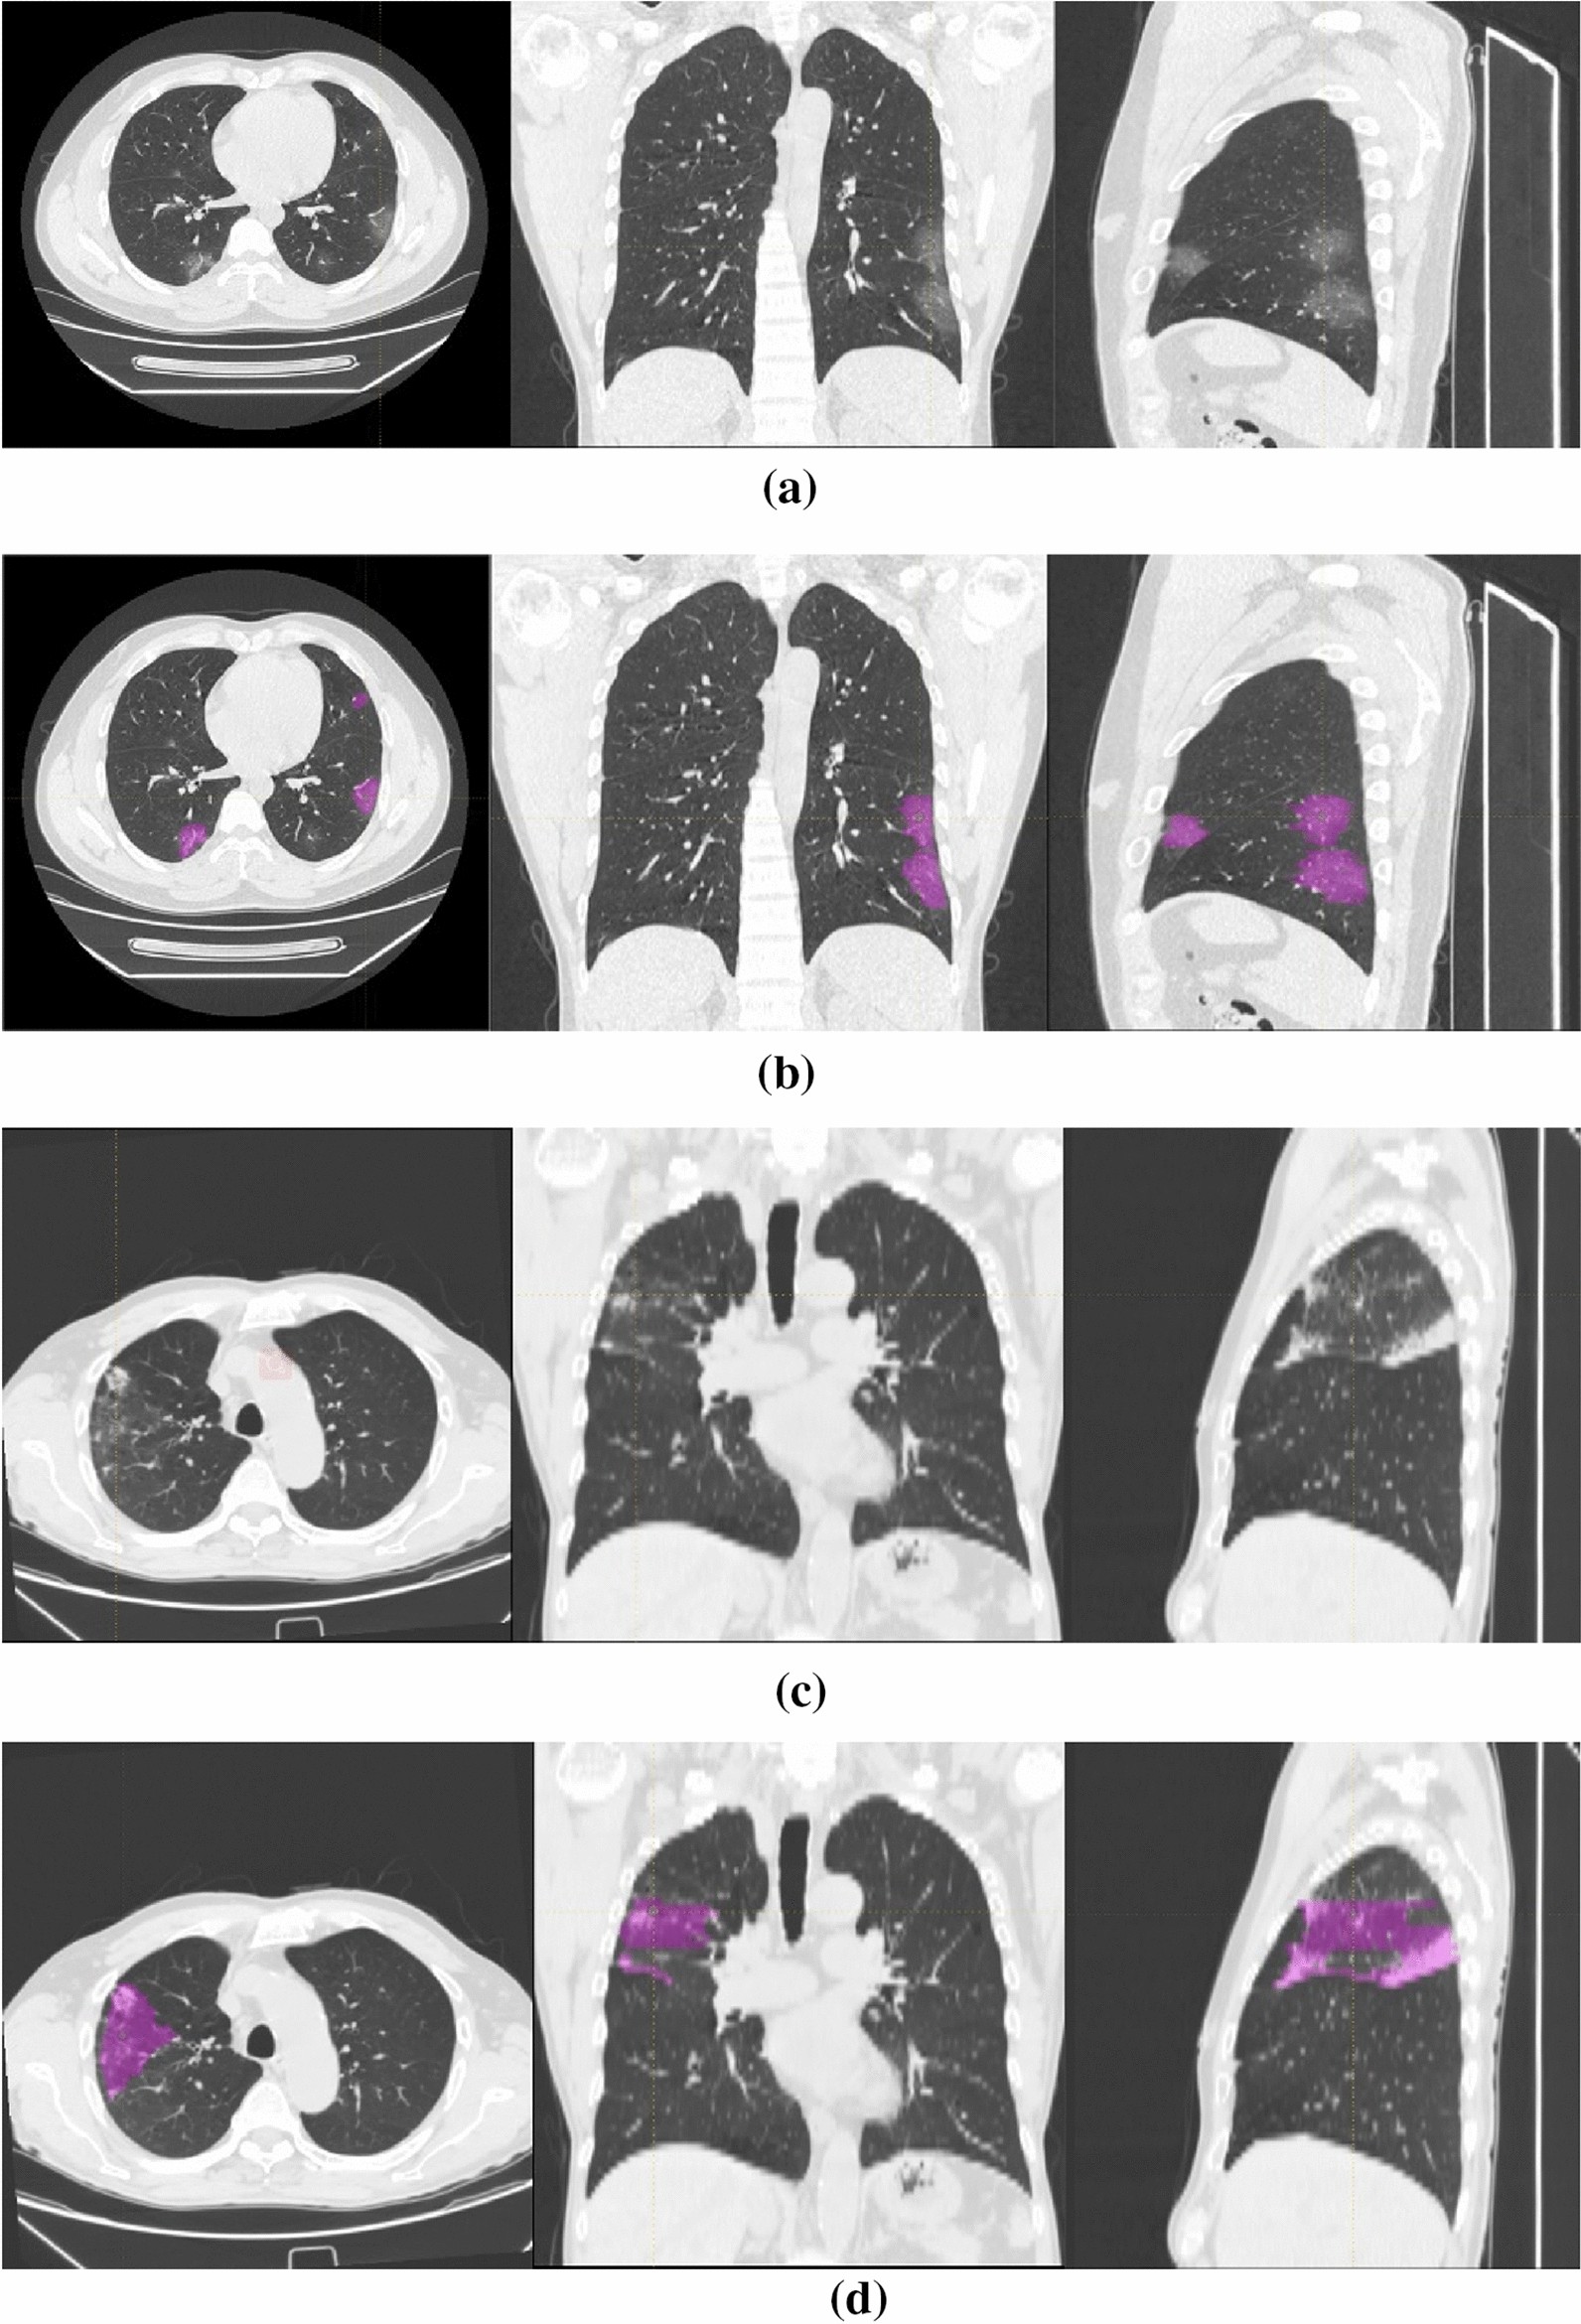

Figure 2

Image examples in different patient groups. From top to bottom: (a,b) a 35-year-old male with COVID-19 and COVID-19 lesion labeling (multiple ground-glass opacity, GGO); (c,d) a 77-year-old male with other pneumonia and other pneumonia lesion labeling (multiple patches and cloud floccules).